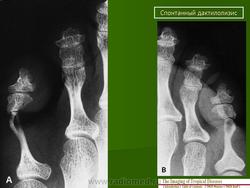

Аингум (ainhum) - спонтанный дактилолизис, описал Da Silva Lima (1852,1867).

Клиника аингума проявляется в виде кольцевидной перетяжки различной ширины с явлениями склероза преимущественно в области пятых пальцев стоп, иногда кистей. В результате дегенерации жировой и фиброзной тканей, постепенного рассасывания кости через 3-5 лет происходит спонтанная безболезненная ампутация пальца.